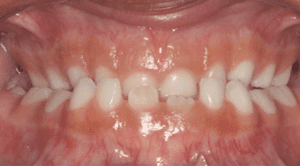

Quando existe o hábito de chupar dedo ou chupeta, dependendo da duração, frequência e intensidade com que é praticado, uma coisa é certa, vai haver repercussão na dimensão óssea dos maxilares, gerando com um tempo um dos tipos de problemas ortodônticos. Alterando, assim, o seu desenvolvimento normal, causando a deformidade abaixo, chamada de Mordida Aberta.

A criança com mordida aberta não consegue o corte dos alimentos com os dentes anteriores. A mordida aberta impede o contato, alterando a função dos dentes e o estímulo normal.